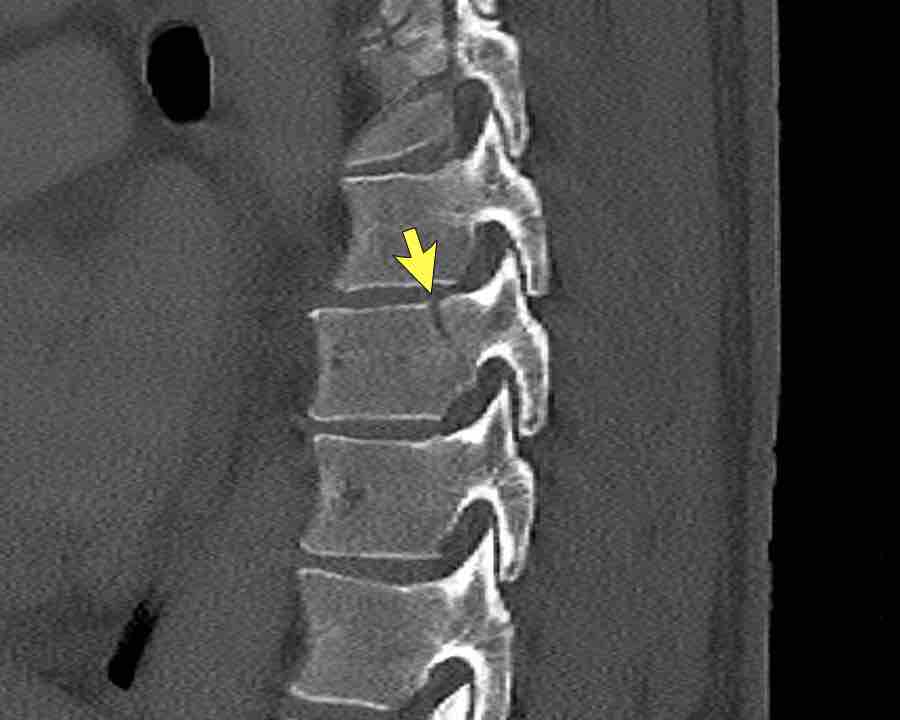

Scroll through the images.

What is the highest AO-type of injury?

Any additional findings?

Findings

- Subtle widening of the interspinous distance (white circle)

- Small avulsion fracture spinous process (yellow arrow)

- Compression fracture with involvement of one endplate and posterior wall (1+2 points)

Conclusion

Injury type B2 + A3